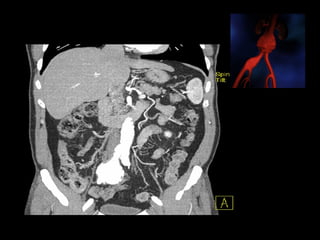

Fenestrated graftFenestrated graft

http://www.perfuse.netVascular surgery @ Tallaght